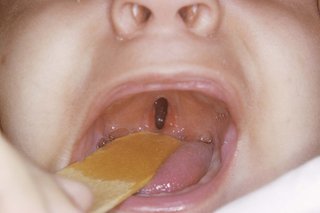

A cleft palate may just be an opening at the back of the mouth, or it may be a split in the palate that runs all the way to the front of the mouth.

The inside of a baby's open mouth showing a narrow hole in the palate at the back of the throat

Sometimes it can be hidden by the lining of the roof of the mouth.